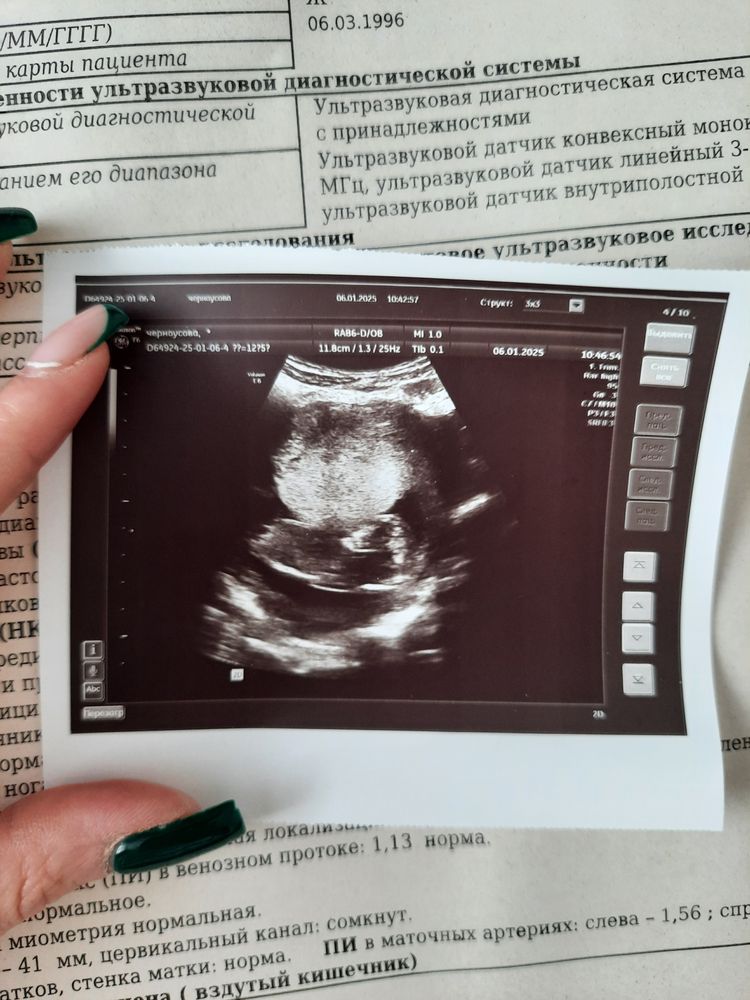

Врач-узи сказала, что визуализация сильно затруднена, поэтому "напишем, что носовая кость есть". Твп мерила долго, намерила 2,3 мм. Говорит норма. По размерам обгоняем срок на 1 день (поставили 12+6). Сердцебиение 159 ударов в минуту, шейка 41мм.

Дала фотку малыша, на которой вообще нет человеческих очертаний, хотя в момент узи фигура малыша была.